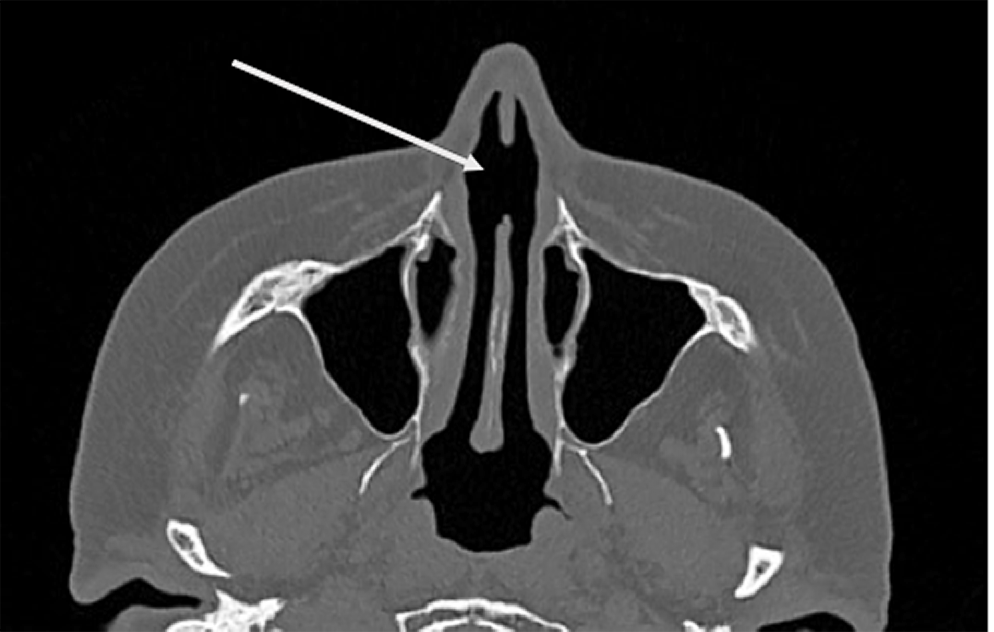

Инструментальные исследования: компьютерная томография (КТ) органов грудной клетки (рис. 5), в верхних долях обоих легких участки фиброза, в том числе типа «матового стекла», очень низкой интенсивности, объемные образования и участки патологической плотности в паренхиме легких и средостении не выявлены. Мультиспиральная компьютерная томография (МСКТ) лицевого скелета (рис. 6) — перфорация перегородки носа, неравномерное утолщение слизистой оболочки нижних отделов верхнечелюстных пазух.

Fig. 6. МCT sinus protocol. Perforation in the area of the cartilaginous part of the nasal septum for about 14 mm